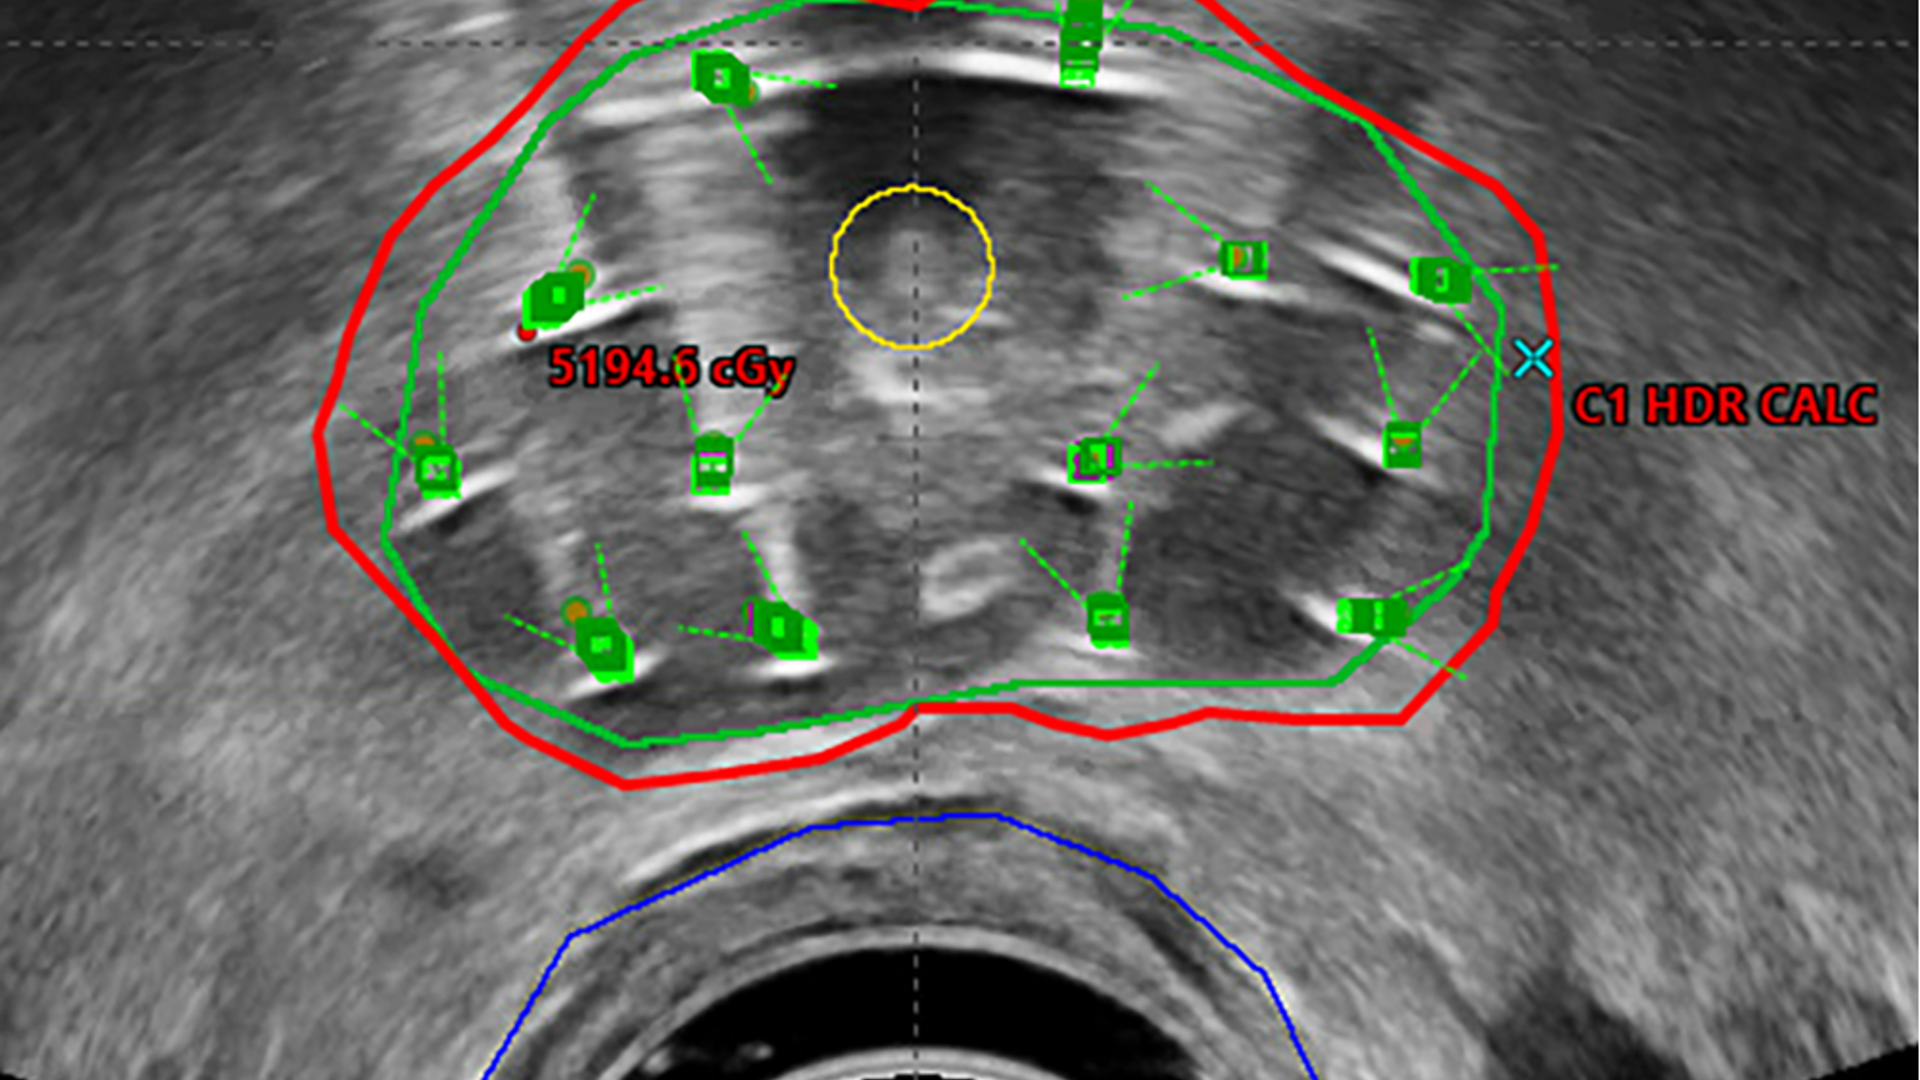

Ultrasound image depicts prostate and surrounding structures with brachytherapy pellet implantation

Figure 1: Axial intraprocedural ultrasound image. Outlines include the prostate (green); the urethra (yellow); the rectum (blue); and radiation dose (red). Transperineal needles are noted as green squares.

A total of 13 catheters were inserted into the prostate mid-gland (Figure 1) and under axial and sagittal guidance advanced to the prostate base. At this point, aerated jelly was mixed and injected into the bladder via the Foley catheter to improve visualization of the urethra on ultrasound, and a second set of images acquired.